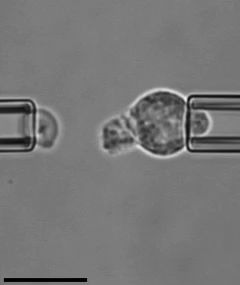

Tạo Kính Hiển Vi Có Cấu Trúc Tích Hợp